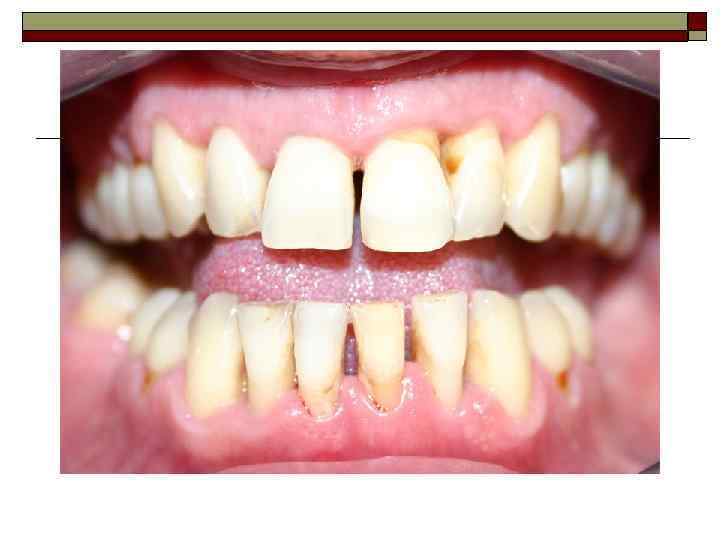

II. Пародонтит — воспаление тканей пародонта, характеризующееся прогрессирующей деструкцией периодонта и кости. Тяжесть: легкая, средняя, тяжелая. Течение: острое, хроническое, обострение (в том числе абсцедирование), ремиссия. Распространенность процесса: локализованный, генерализованный.

III. Пародонтоз — дистрофическое поражение пародонта. Тяжесть: легкая, средняя, тяжелая. Течение: хроническое, ремиссия. Распространенность процесса: генерализованный.

Перегрузка пародонта Деструктивно-воспалительные процессы могут наблюдаться при различных аномалиях прикуса (глубокий прикус, глубокое резцовое перекрытие, открытый, прогнатический, прогенический прикус и др. ) и положения зубов (скученность зубов); при ранней потере моляров и премоляров; после удаления большого количества зубов (постэкстракционные передвижения зубов); при неправильном определении показаний к мостовидному, особенно металлокерами-ческому, протезированию, неправильно сформированном преддверии полости рта; после хейло- и уранопластики; при бруксизме (ночное скрежетание зубами) и др.